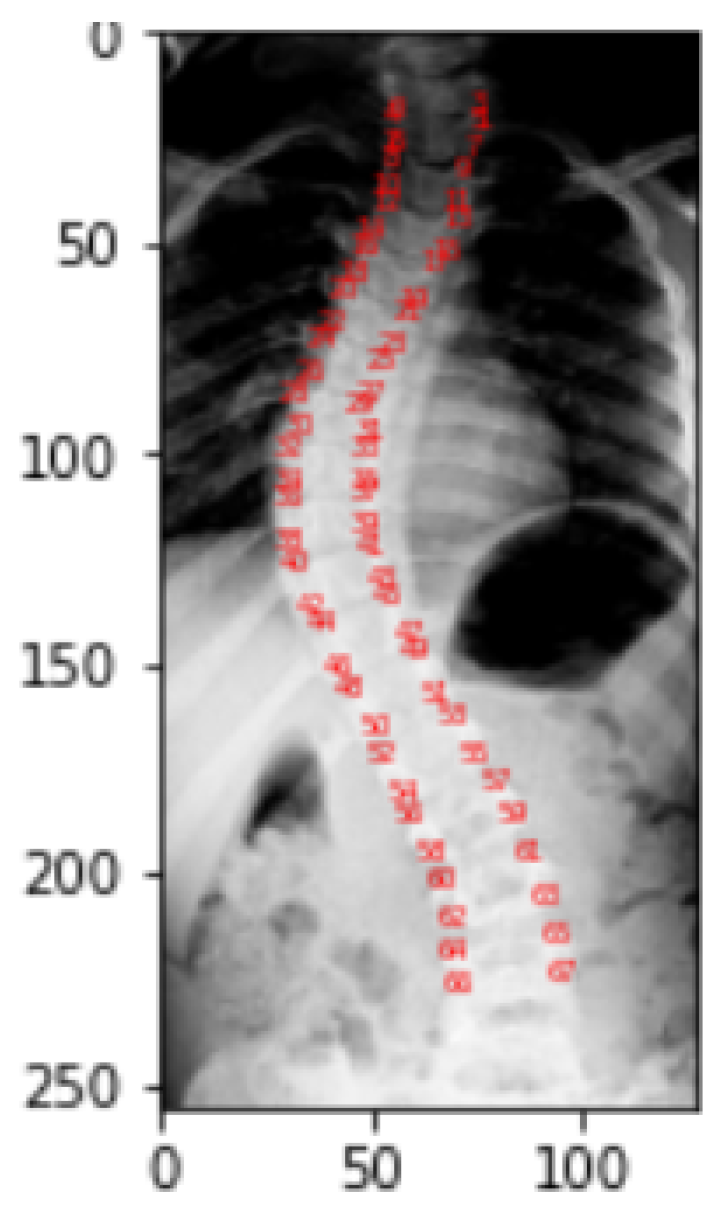

This visualization is only done to help the viewer better see and comprehend the spine part of the X-ray picture. Figure 10 gives the visualization of landmarks. Landmark values of a picture correspond to the location of pixel in a particular image for which it is obtained. In the dataset, each picture in the landmarks file has CSV values that correspond to the pixel position in the specific image for which they were obtained. As a part of the representation process, these landmark values are transformed into arrays, which are then reshaped into two columns for a single picture as x and y coordinates, and finally mapped to pixel values.

To identify the spine portion, the land marking is performed by reading the image into arrays and converting theses array into two columns of x and y coordinates leading to the transformation into pixel values. Plot of these pixel values highlight the spine area. The red highlighted dash lines around the spine in Figure 17 refers to the landmarks of the spine.

Figure 10. Visualization of Landmarks on Original Images.

Figure 17. Visualization of landmarks.